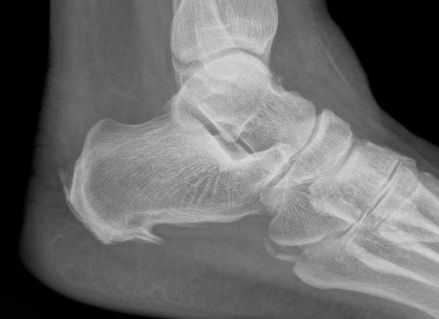

X-ray

Insertional achilles tendon spurs

- also present in asymptomatic patients

Calcification of bone-tendon interface with spur

Haglund's Deformity

- bony protuberance of posterosuperior calcaneus

Pavlov's parallel pitch lines

- lateral weight bearing x-ray

- draw parallel pitch lines

- defines Haglund's deformity to be removed (above second line)

Fowler's angle - Normal < 70° / Abnormal > 80°